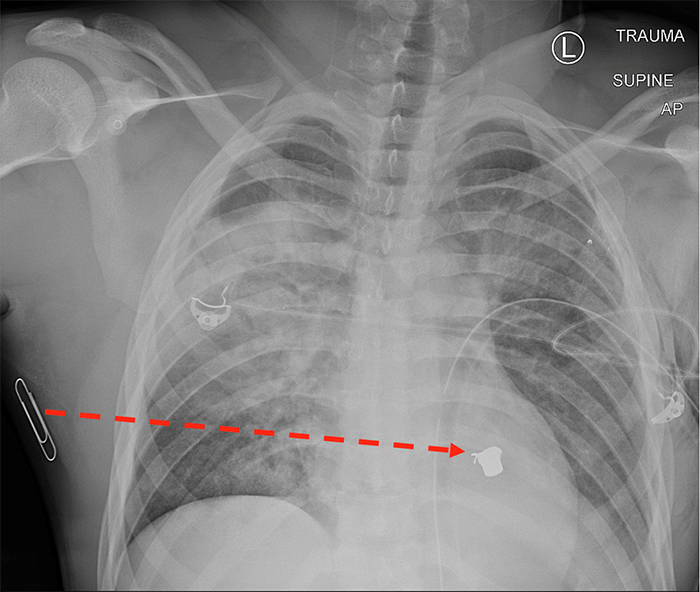

A 29-year old man was transferred to our level 1 trauma center from a community emergency department after sustaining a gunshot wound to his right axilla (marked by a closed paperclip signifying an anterior wound on chest X ray in Fig 1). He was found to have a contralateral, left-sided pneumothorax on chest X ray at the community emergency department and a left-sided tube thoracostomy was inserted prior to transfer. On arrival at our trauma center, the patient was hemodynamically normal and neurologically intact with minimal hypoxia and no respiratory distress. Trauma survey was notable only for a single gunshot wound to the right axilla along the anterior axillary line. Focused assessment with sonography in trauma (FAST) exam was unremarkable without evidence of pericardial effusion. Chest X ray revealed a right-sided pulmonary contusion, as well as a bullet overlying the left mediastinum. The proposed trajectory from entry to bullet is Transmediastinal, as indicated by the dashed line in Figure 1.

Figure 1: Chest X ray of patient with Transmediastinal gunshot wound. Dotted red line depicts bullet trajectory implied by skin wound (marked by paper clip) and location of bullet on X ray.